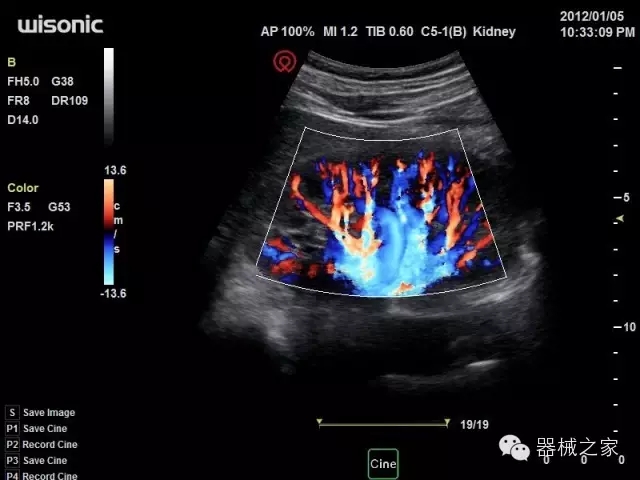

品牌:華聲醫(yī)療(WISONIC)

官方網(wǎng)站:www.wisonic.cn

經(jīng)典產(chǎn)品:四葉草

臨床圖片賞析

產(chǎn)品特點

·全球目前唯一一款配備主機雙探頭接口,整機重量(含電池)在5公斤以內(nèi)的便攜式彩超;

·一款互聯(lián)網(wǎng)彩超,只要有手機信號的地方就可以非常方便地實現(xiàn)遠程會診和病案調(diào)?。?/span>

·鎂鋁合金外殼,堅固可靠耐用;

·獨有的HoloTM PW 實時3取樣門PW成像技術(shù),精確進行血管診斷;

·一鍵優(yōu)化B、Color、PW,Auto Doppler自動識別血管位置、偏轉(zhuǎn)角度等,提高工作效率;

·30°超廣角精細偏轉(zhuǎn)成像技術(shù),更優(yōu)異的頻譜圖像;

·W+智能搜索引擎,快速尋找圖像;

·SSD、USB3.0保障開機快,導(dǎo)出圖像更快,減少等待時間;

·WIFI、網(wǎng)口、3G,多重聯(lián)網(wǎng)方式,全天候保障云端備份,不再擔(dān)心圖像丟失;

CFDA注冊證編號

·粵械注準(zhǔn)201522231208